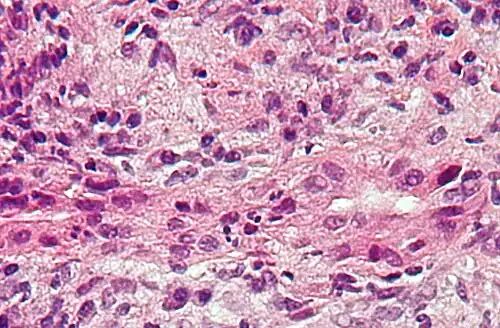

| Micrograph of PBC showing bile duct inflammation and injury, H&E stain | |

On microscopic examination of liver biopsy specimens, PBC is characterized by chronic, nonsuppurative inflammation, which surrounds and destroys interlobular and septal bile ducts. These histopathologic findings in primary biliary cholangitis include:[32]

- Inflammation of the bile ducts, characterized by intraepithelial lymphocytes

- Periductal epithelioid granulomas.

- Proliferation of bile ductules

- Fibrosis (scarring)